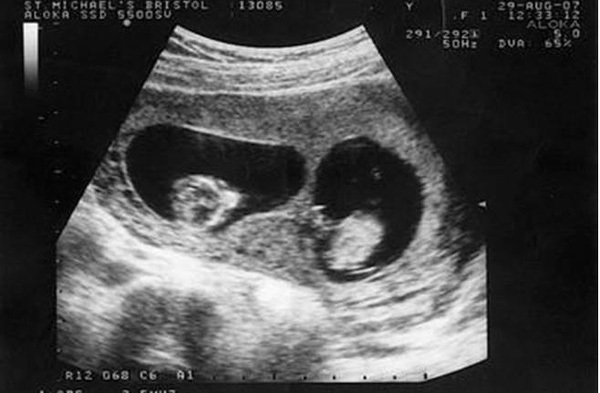

Khi mang bầu, chị Tiểu Mai và gia đình vô cùng hạnh phúc khi biết sắp chào đón cặp song sinh. Tuy nhiên, đến ngày sinh, không chỉ riêng gia đình mà đến ngay cả chị Tiểu Mai cũng cảm thấy vô cùng choáng váng khi sự thật lại không như khi siêu âm.

Cả gia đình đã hi vọng hai bé sinh đôi chào đời nhưng họ đã lặng người vì bất ngờ khi “chứng kiến” cảnh tượng mà có nằm mơ họ cũng không thể tưởng tượng nổi.

Trong thời kì đầu mang thai, Tiểu Mai, 25 tuổi, người Trung Quốc đi siêu âm và bác sĩ thông báo cô đang mang trong mình thai sinh đôi. Bác sĩ có dặn cô tháng sau tới siêu âm định kỳ nhưng vì bệnh viện ở xa nhà nên Tiểu Mai không tới khám lại nữa.

Trong quá trình mang thai, Tiểu Mai chỉ đi khám 3 lần và sinh con ở tuần thứ 37. Cả gia đình đều chuẩn bị sẵn tâm lý vui mừng để đón 2 đứa trẻ chào đời nhưng sau khi đưa được hai em bé ra ngoài, các bác sĩ nhìn thấy một đôi chân nữa trong bụng Tiểu Mai, họ lập tức đưa em bé thứ 3 ra ngoài trong sự ngỡ ngàng.

Trên thực tế, Tiểu Mai đã mang thai 3 đứa trẻ, 2 trai 1 gái nhưng khi siêu âm bác sĩ không hề thấy sự hiện diện của đứa trẻ thứ ba nên đã tiết lộ kết quả là sinh đôi. Họ cũng cho biết, có thể 2 đứa bé kia đã nằm chắn đứa bé này nên khi siêu âm không nhìn thấy được. Thật may mắn, đứa bé thứ 3 ra đời rất khỏe mạnh. Vậy là niềm vui của gia đình lại được nhân lên khi mà đáng lẽ họ chỉ có 2 đứa con thì giờ lại xuất hiện thêm một thiên thần nhỏ thứ 3.

Tuy nhiên, không phải gia đình nào cũng được may mắn như vậy nên bác sĩ khuyên các thai phụ lưu ý nên đi khám thai thường xuyên và nghe theo chỉ dẫn của bác sĩ để đón con khỏe mạnh chào đời.